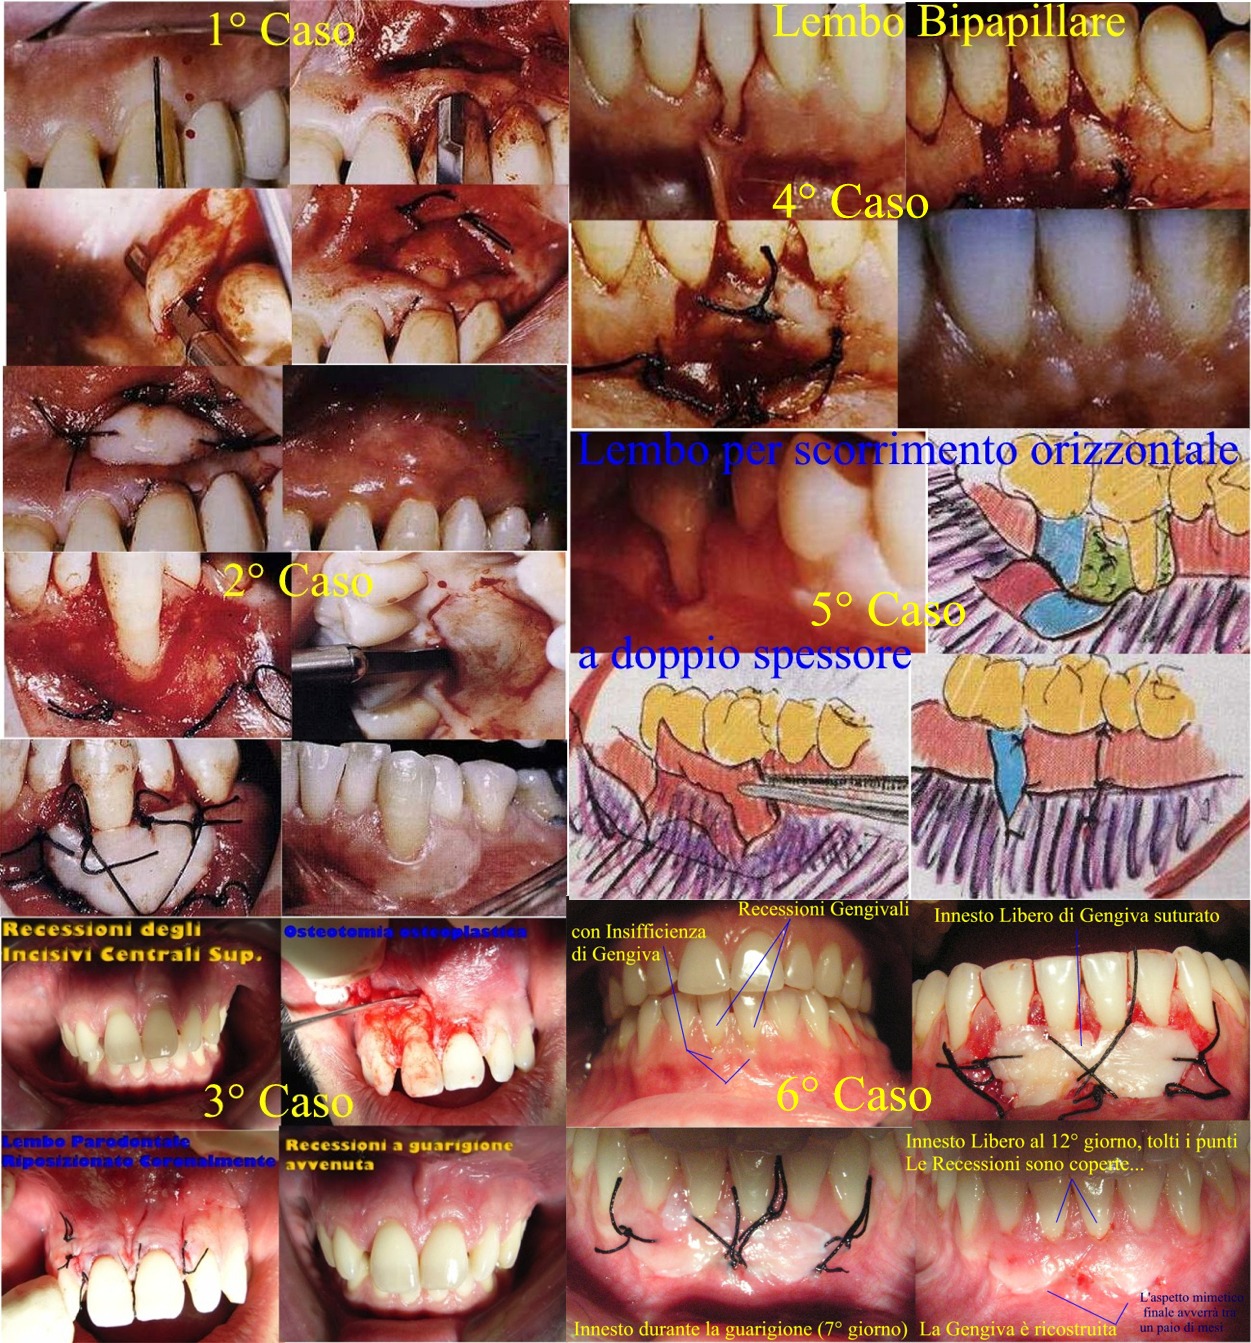

Caro Signor Alessio, Buongiorno. Il Dottor Paolo De Carli, come sempre, è stato chiarissimo. Aggiungo, da Parodontologo quale sono, che l'innesto Libero di Gengiva per ricostituire una "banda sufficiente di Gengiva Aderente, è un intervento usuale, tranquillo e sicuro. Poi se chiede se esistono altri tipi di interventi, le rispondo, si certo. Esistono tanti interventi diversi per approfondire il Fornice come per esempio l'Intervento di Edlan Mejchar che però è molto complesso e bisogna saperlo fare. Poi ci sono tantissimi altri interventi e metodiche, di cui per darle un'idea le posto una parziale "raccolta" in un Post di miei Interventi. Detto questo, dal suo racconto , il suo Parodontologo sta agendo benissimo e con competenza, non spetterebbe a me dirlo perché non sono qui per giudicare. Dico così per farle capire che, avendo Egli prima ricostruito o Rigenerato (non so quale delle due metodiche siano state applicate) l'osso e poi avendo pianificato l'aumento della gengiva aderente ed approfondimento del fornice con un innesto con prelievo palatino, evidentemente, questo è l'intervento di Elezione scelto per la situazione Clinica di Suo Figlio. Oggi giorno si può proteggere il "Letto ricevente" ed "il Letto donatore" con impacco chirurgico parodontale il primo e con varie metodiche tra cui cerotti chirurgici che provengono dall'uso in chirurgia Maxillo Facciale e coi farmaci giusti, il dolore e le complicanze post-operatorie sono ridotte al minimo o addirittura non ce ne sono. Certo un po' di dolore ci sarà, ma è compito del suo Dentista Spiegare ed Informare sul decorso postoperatorio, non è mio compito. Le dico solo di Fidarsi e di avere Stima nel suo Parodontologo, che diamine. Lasci perdere i materiali artificiali o di altra natura. Non c'è ancora una casistica Clinica Valida e soprattutto "lunga nel tempo". Gli innesti Liberi di Gengiva invece hanno alle spalle oltre 50 anni di "storia" e di "sempre più raffinate" tecniche chirurgiche! Stia tranquillo Lei e soprattutto trasmetta questa sua serenità a suo figlio :) Cari saluti ed in bocca al "Lupo"